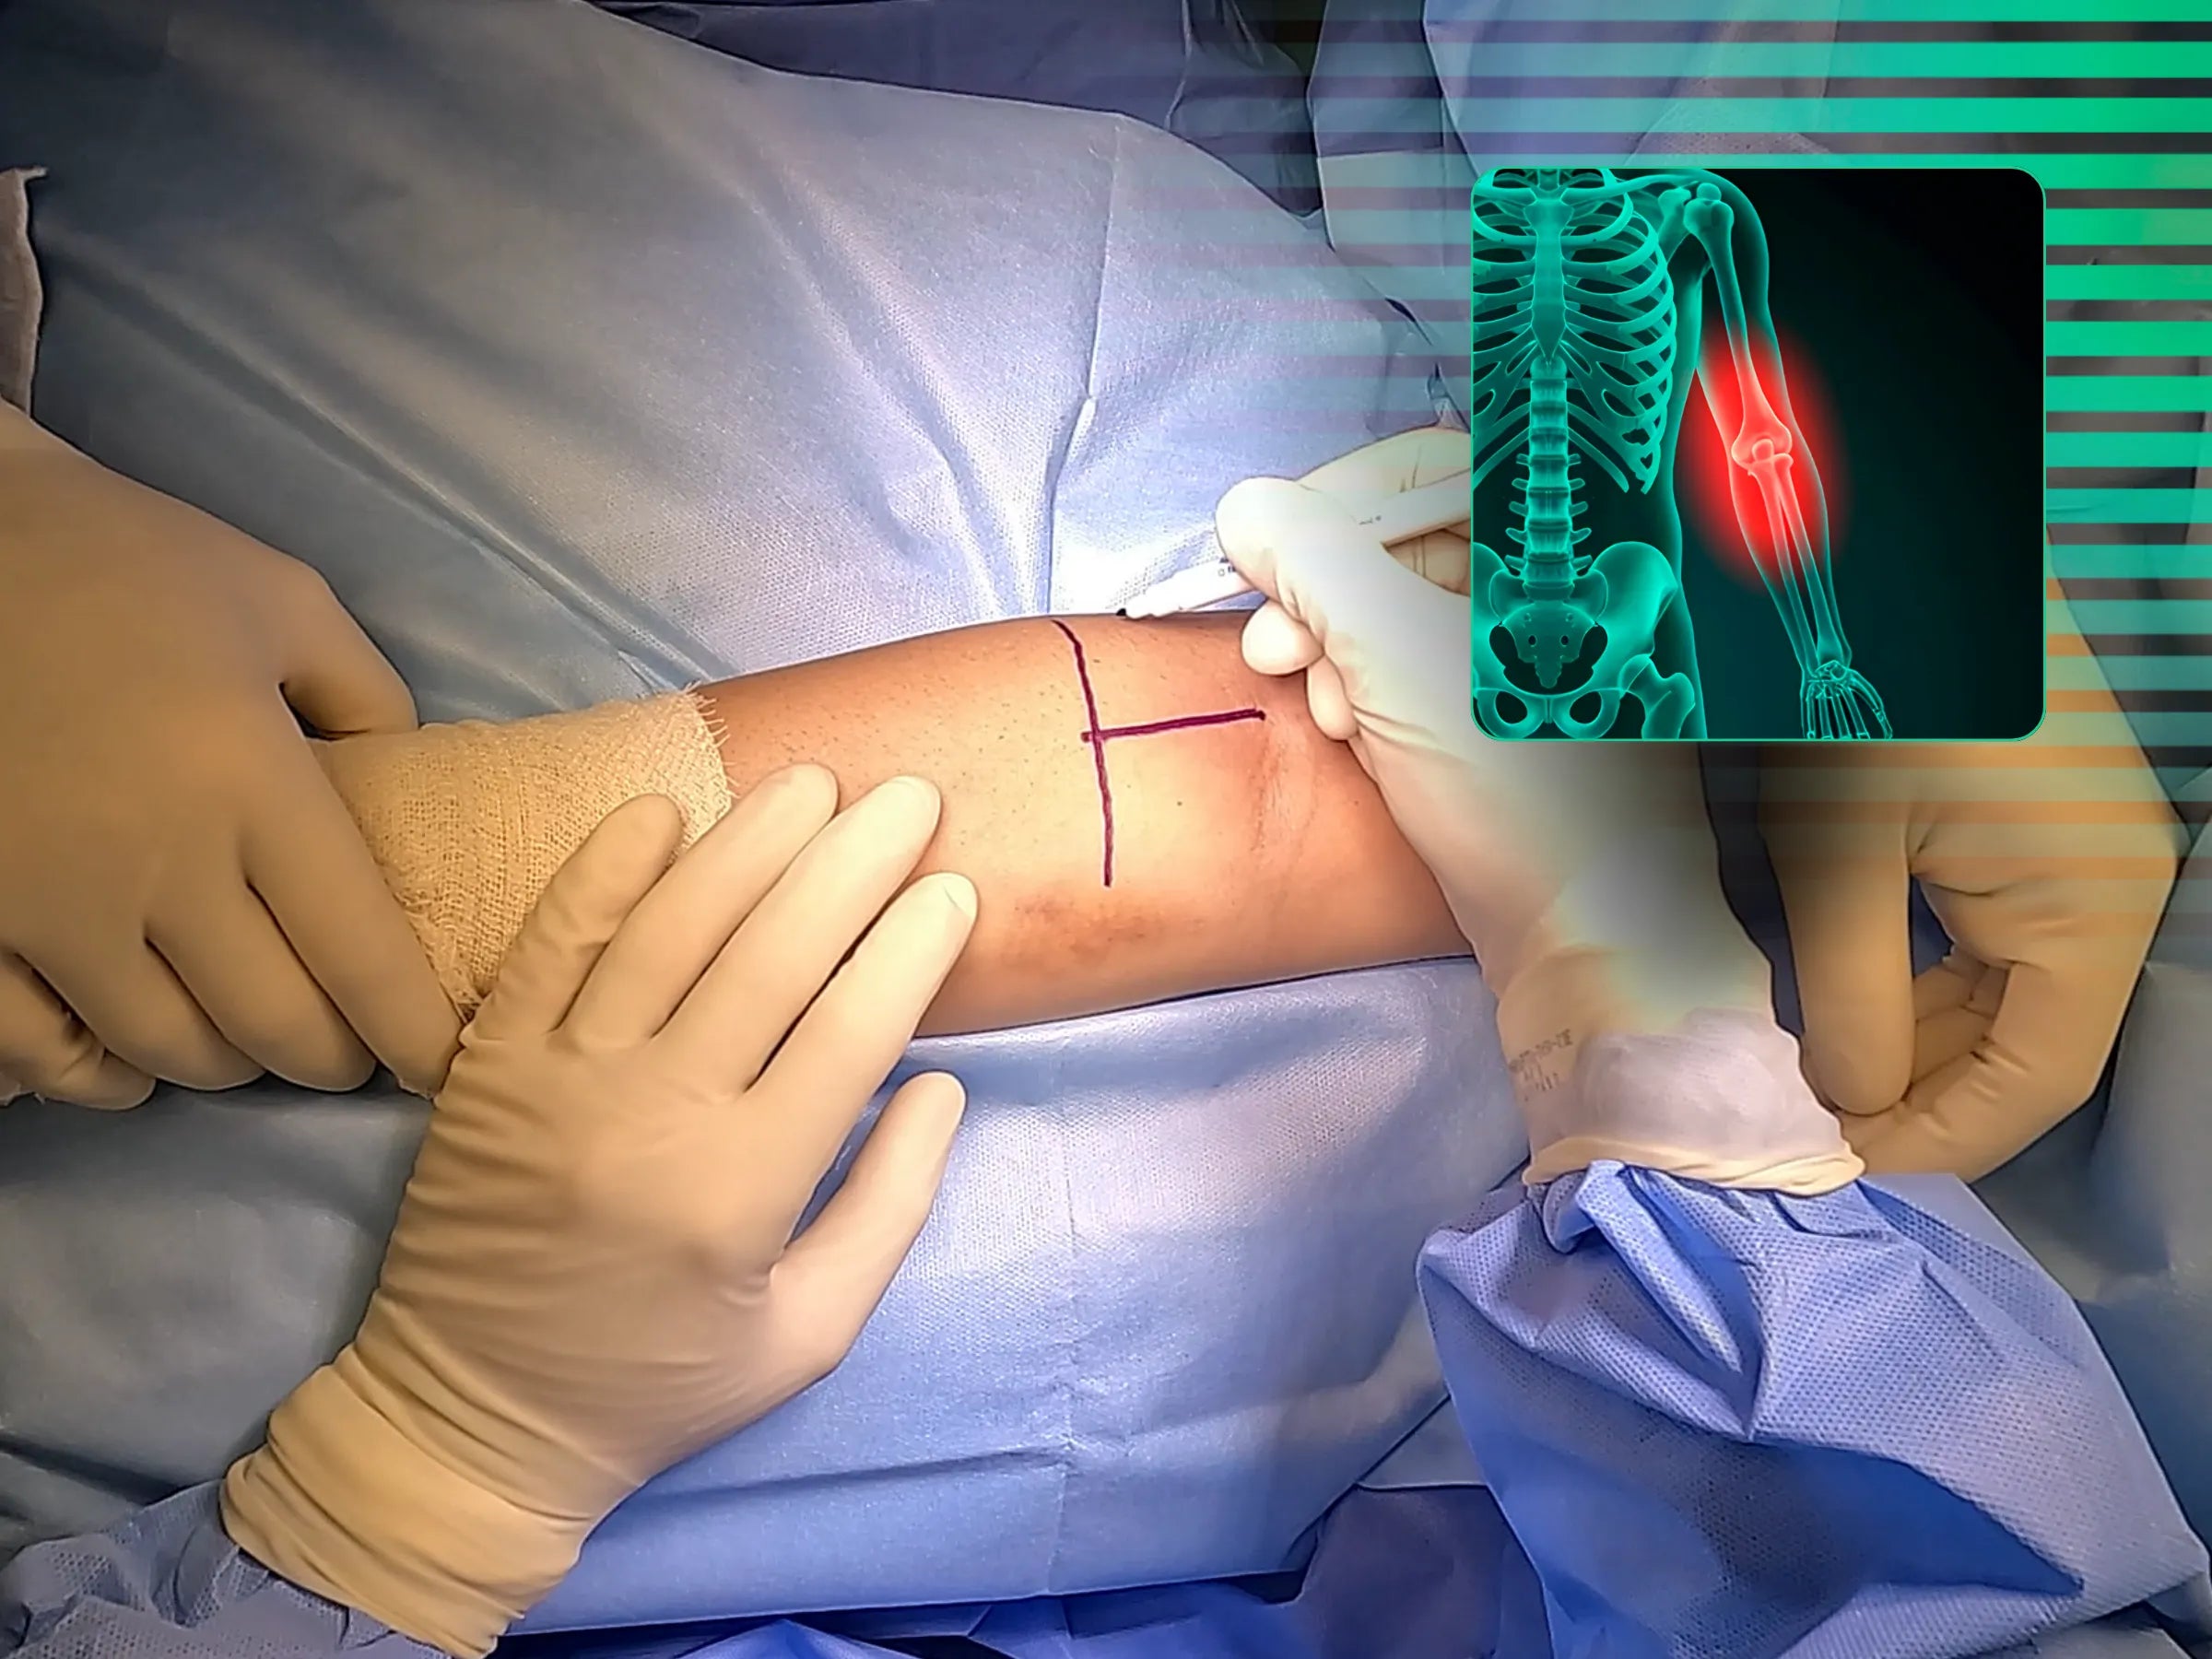

- Avaliação e Planejamento: Palpação do limite do braquiorradial e uso de fluoroscopia para localizar a tuberosidade do rádio. Acesso cutâneo planejado para evitar lesão muscular e dissecção precisa da fáscia.

- Exposição do Sítio de Reinserção: Visualização da tuberosidade do rádio com supinação total do antebraço, expondo o local da desinserção do bíceps.

- Preparação e Sutura do Tendão: Modelagem triangular da extremidade tendínea para facilitar a introdução. Sutura com material Arthrex, ligeiramente justa para estabilidade.